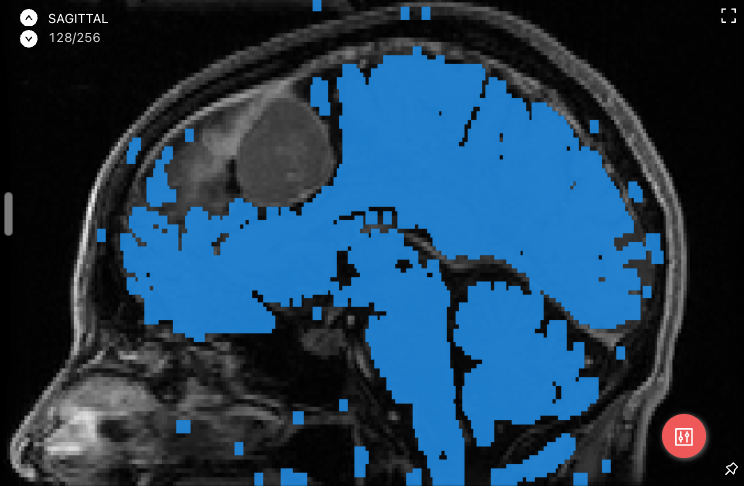

Example of median smoothing:

->

The larger the kernel size, the more aggressive the smoothing.